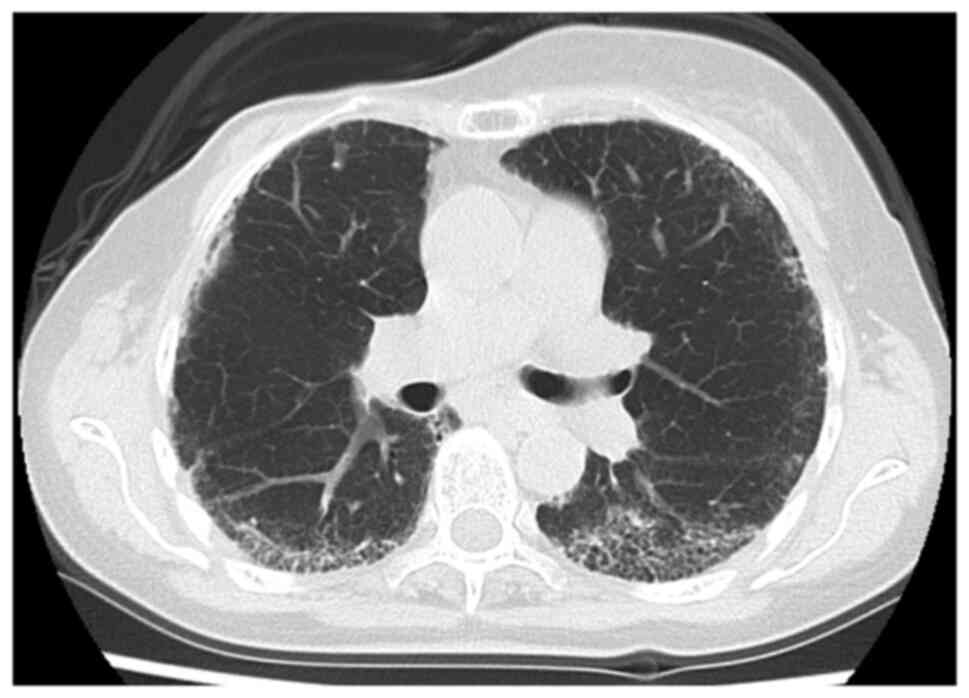

At 63 years old, contrast-enhanced computed tomography (CT) performed as postoperative follow-up indicated brain metastasis in the right occipital lobe without liver, lung, or bone metastasis. She underwent γ-knife radiosurgery (20 Gy) followed by the administration of perutuzumab, trastuzumab, and weekly paclitaxel. After four cycles of perutuzumab, trastuzumab, and weekly paclitaxel, she experienced shortness of breath with minimal exertion, so the fifth course was canceled. CT revealed ground-glass opacities and linear shadows in the peripheral lower lobes of both lungs (Fig. 1). Although the development of lung involvement associated with breast cancer such as carcinomatous lymphangitis was initially suspected, because of the increase in CA 15-3, we investigated other possible causes of ILD (Fig. 2). From only CT image, the possibility of interstitial lung disease due to trastuzumab or pertuzumab cannot be ruled out (19). Bilateral sclerodactyly and facial skin thickness were found on clinical examination without a history of Raynaud's phenomenon and the finding of nail fold bleeding. A test for anti-nuclear antibodies with a nucleolar pattern was positive, at a titer of 1:320. Anti-double stranded DNA antibody, specific antibodies against centromere, SSA/SSB, Scl-70, RNP, and RNA polymerase III were negative. Pulmonary function tests showed a severely reduced %VC of 50.8%, indicating restrictive ventilatory impairment. Skin biopsies taken from the left index finger base and extension side of the left elbow demonstrated increased thickness of the dermis composed of broad and sclerotic collagen bundles extending to the underlying subcutis without inflammatory cell infiltration in hematoxylin and eosin stained-samples. These findings were consistent with the late stage of scleroderma (Fig. 3). From these findings, the diagnosis of SSc-ILD was made according to the diagnostic criteria for SSc proposed by the Ministry of Health, Labour and Welfare of Japan. The treatment for recurrent breast cancer was discontinued, and combination prednisone (PSL) (15 mg/day) and intravenous cyclophosphamide (IVCY) (500 mg/4 weeks) therapy was administered for induction treatment of SSc-ILD. PSL was tapered and discontinued at 1 year and IVCY was given five times in total. At 6 months after the start of treatment, her symptoms, including cough and dyspnea, had improved. CA 15-3 and KL-6 levels decreased simultaneously, reflecting the therapeutic effect (Fig. 2), and CT showed improvement in the ground-glass opacities in the peripheral lower lobes of both lungs as compared with those before treatment (Fig. 4). This patient is receiving treatment for SSc-ILD. The patient's SSc-ILD has not worsening and her breast cancer has not recurred despite not receiving treatment for four years.

Figure 4

No progression of ground-glass shadows in the peripheral lower lobes of both lungs were seen on chest computed tomography compared with before treatment for sclerosis-interstitial lung disease.